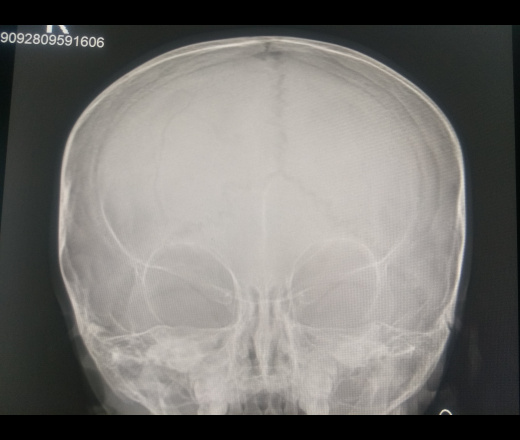

Перелом лобной кости

Пациентка,1 год, упала 4 дня назад с двухметровой высоты. Потери сознания не было. Через четыре дня появилась многократная рвота. Рвота после еды.

Лентовидные просветления в лобной кости справа считаю диплоической веной. Уважаемые коллеги, исправьте если ошибся.

Без костной патологии.